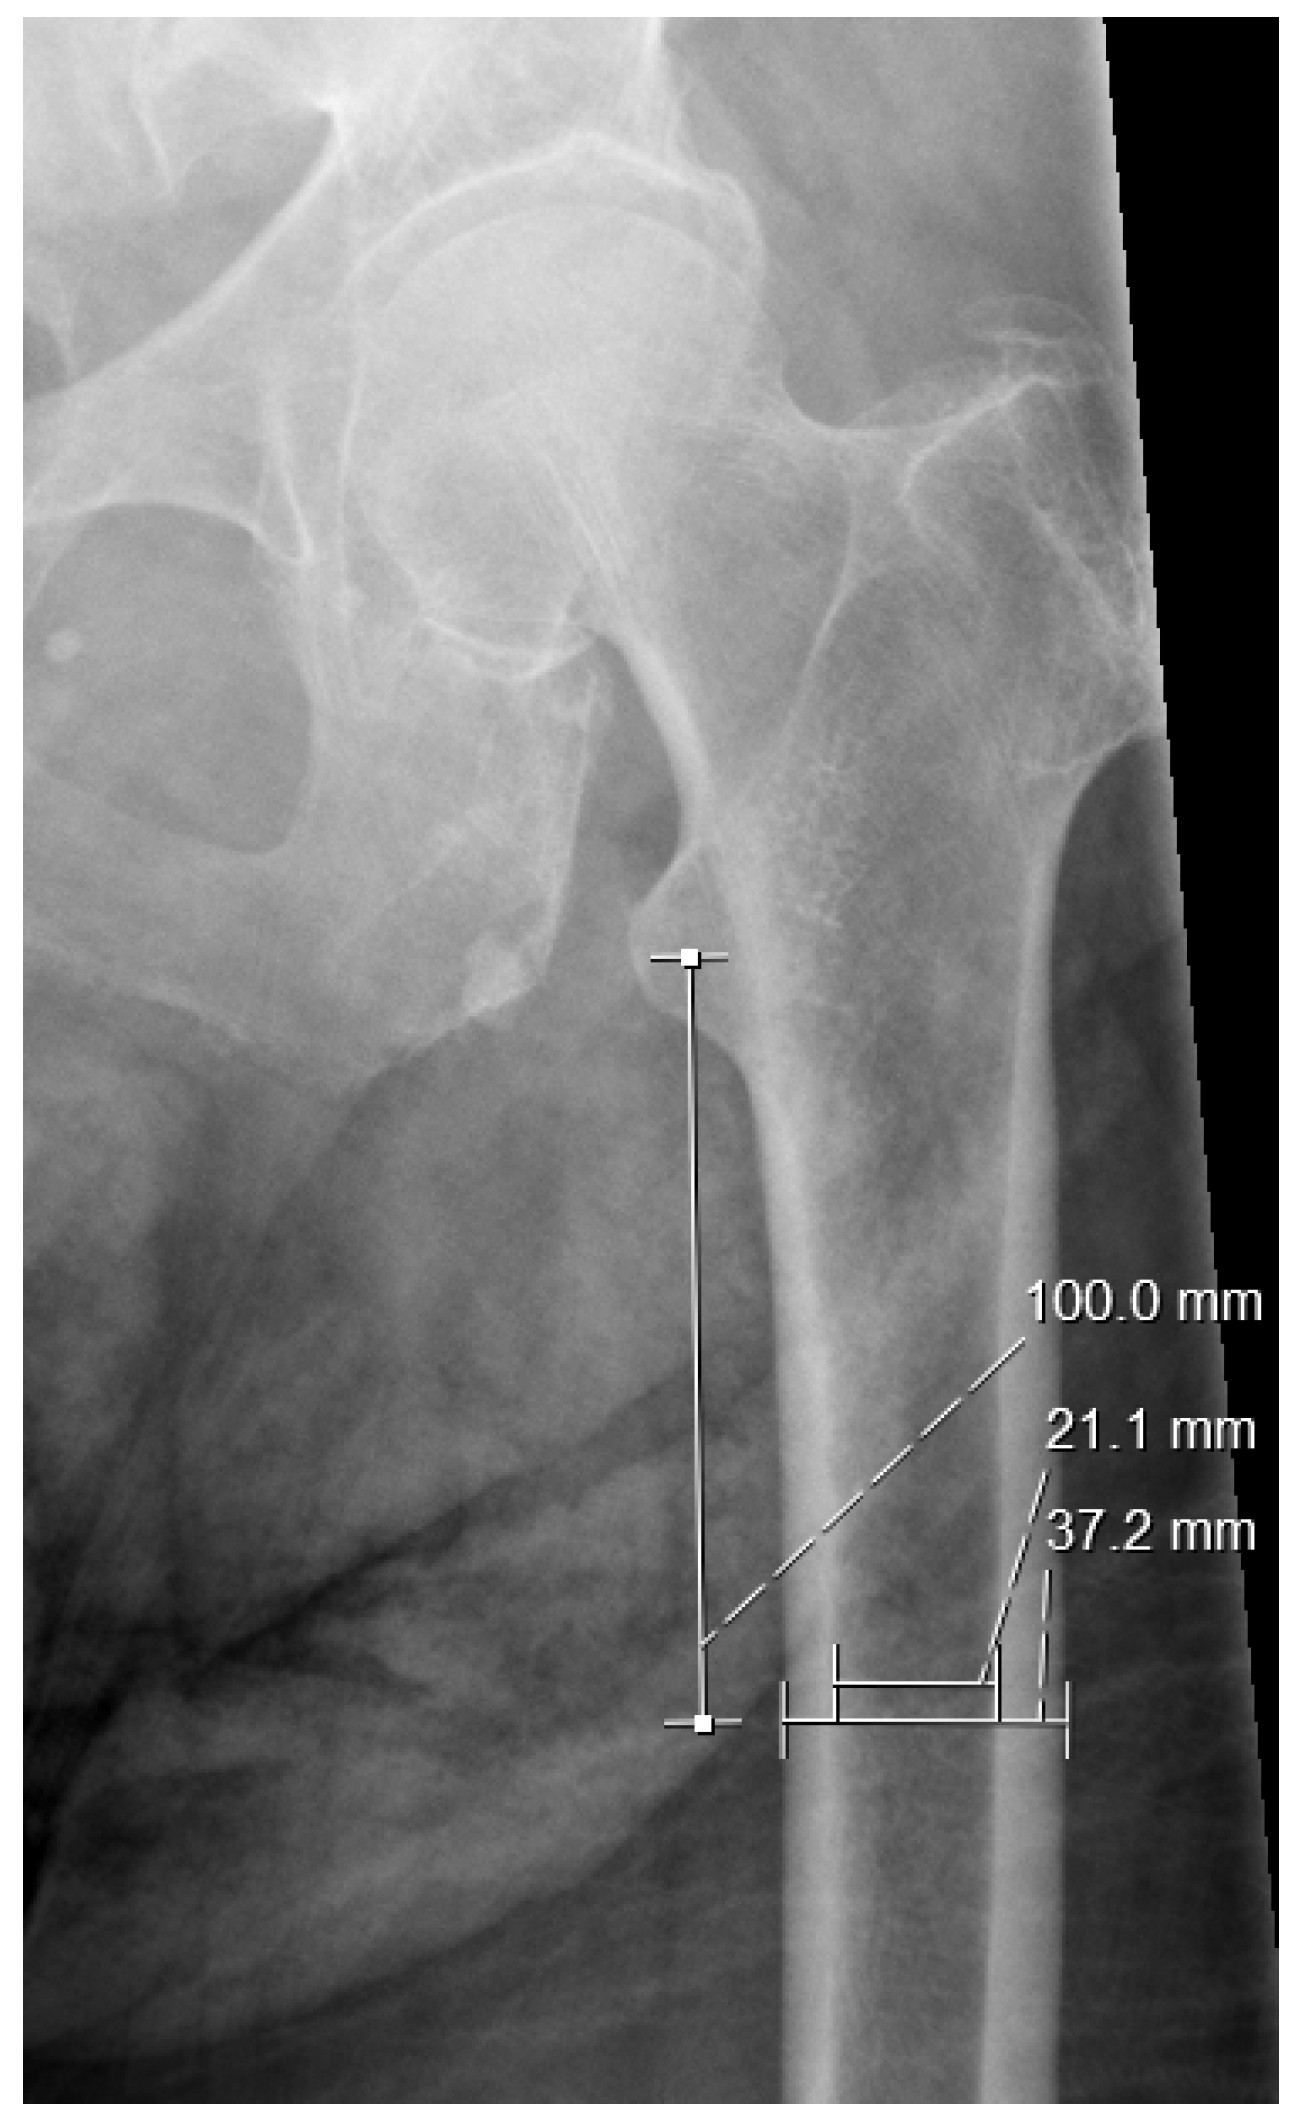

2.3. Measurements

- Noble, P.C.; Alexander, J.W.; Lindahl, L.J.; Yew, D.T.; Granberry, W.M.; Tullos, H.S. The anatomic basis of femoral component design. Clin. Orthop. Relat. Res. 1988, 235, 148–165. [Google Scholar] [CrossRef]

- Dossick, P.H.; Dorr, L.D.; Gruen, T.; Saberi, M.T. Techniques for preoperative planning and postoperative evaluation of noncemented hip arthroplasty. Tech. Orthop. 1991, 6, 1–6. [Google Scholar] [CrossRef]

- Nakaya, R.; Takao, M.; Hamada, H.; Sakai, T.; Sugano, N. Reproducibility of the Dorr classification and its quantitative indices on plain radiographs. Orthop. Traumatol. Surg. Res. 2019, 105, 17–21. [Google Scholar] [CrossRef] [PubMed]

| CW10 | 32.78 (2.94) | 31.30 (3.11) | 0.001 |

| EW10 | 16.15 (2.74) | 15.51 (3.02) | 0.117 |

| EWlt | 27.22 (3.61) | 28.85 (4.60) | 0.006 |

| CTI | 0.51 (0.07) | 0.50 (0.09) | 0.778 |

| CCR | 0.60 (0.11) | 0.55 (0.11) | 0.001 |